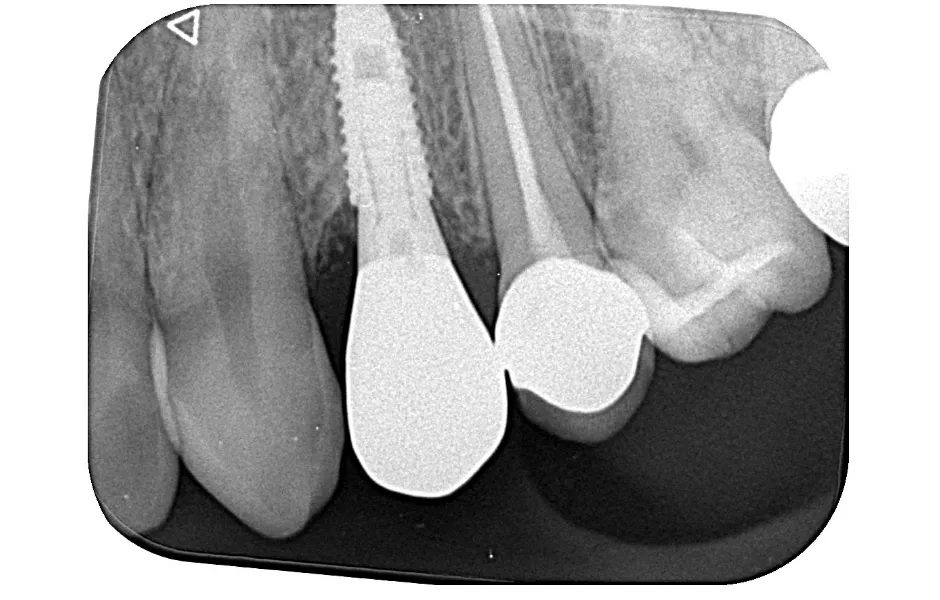

インプラント治療

失った歯を補う方法の1つで、インプラントが歯根の代わりを果たすことで天然歯に近い噛み心地を再現します。当院ではサージカルガイドを使用することで、より精密な埋入を可能とし、術後の痛みや腫れを軽減しています。機能性だけでなく審美性も回復します。